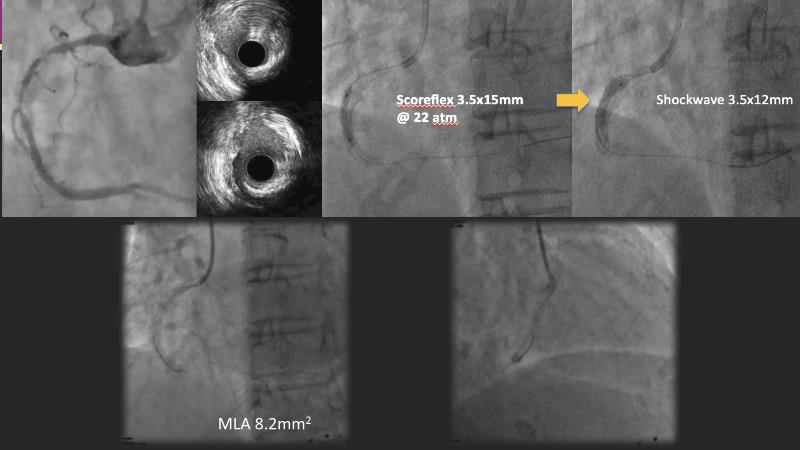

Discover the power of drug-coated balloon (DCB) technology in modern PCI. Understand the mechanism of action, including antiproliferative agents, drug transfer to the vessel wall, and effective inhibitory level and duration of vessel wall retention. Learn how IVUS can guide optimal lesion preparation, and explore the criteria for delivering effective DCB treatment.

- To understand drug coated balloon (DCB) technology (including antiproliferative agents, drug transfer to vessel wall, effective inhibitory level and duration of vessel wall retention)

- To learn how IVUS can guide optimal lesion preparation

- To learn the criteria for optimal lesion preparation prior to DCB application